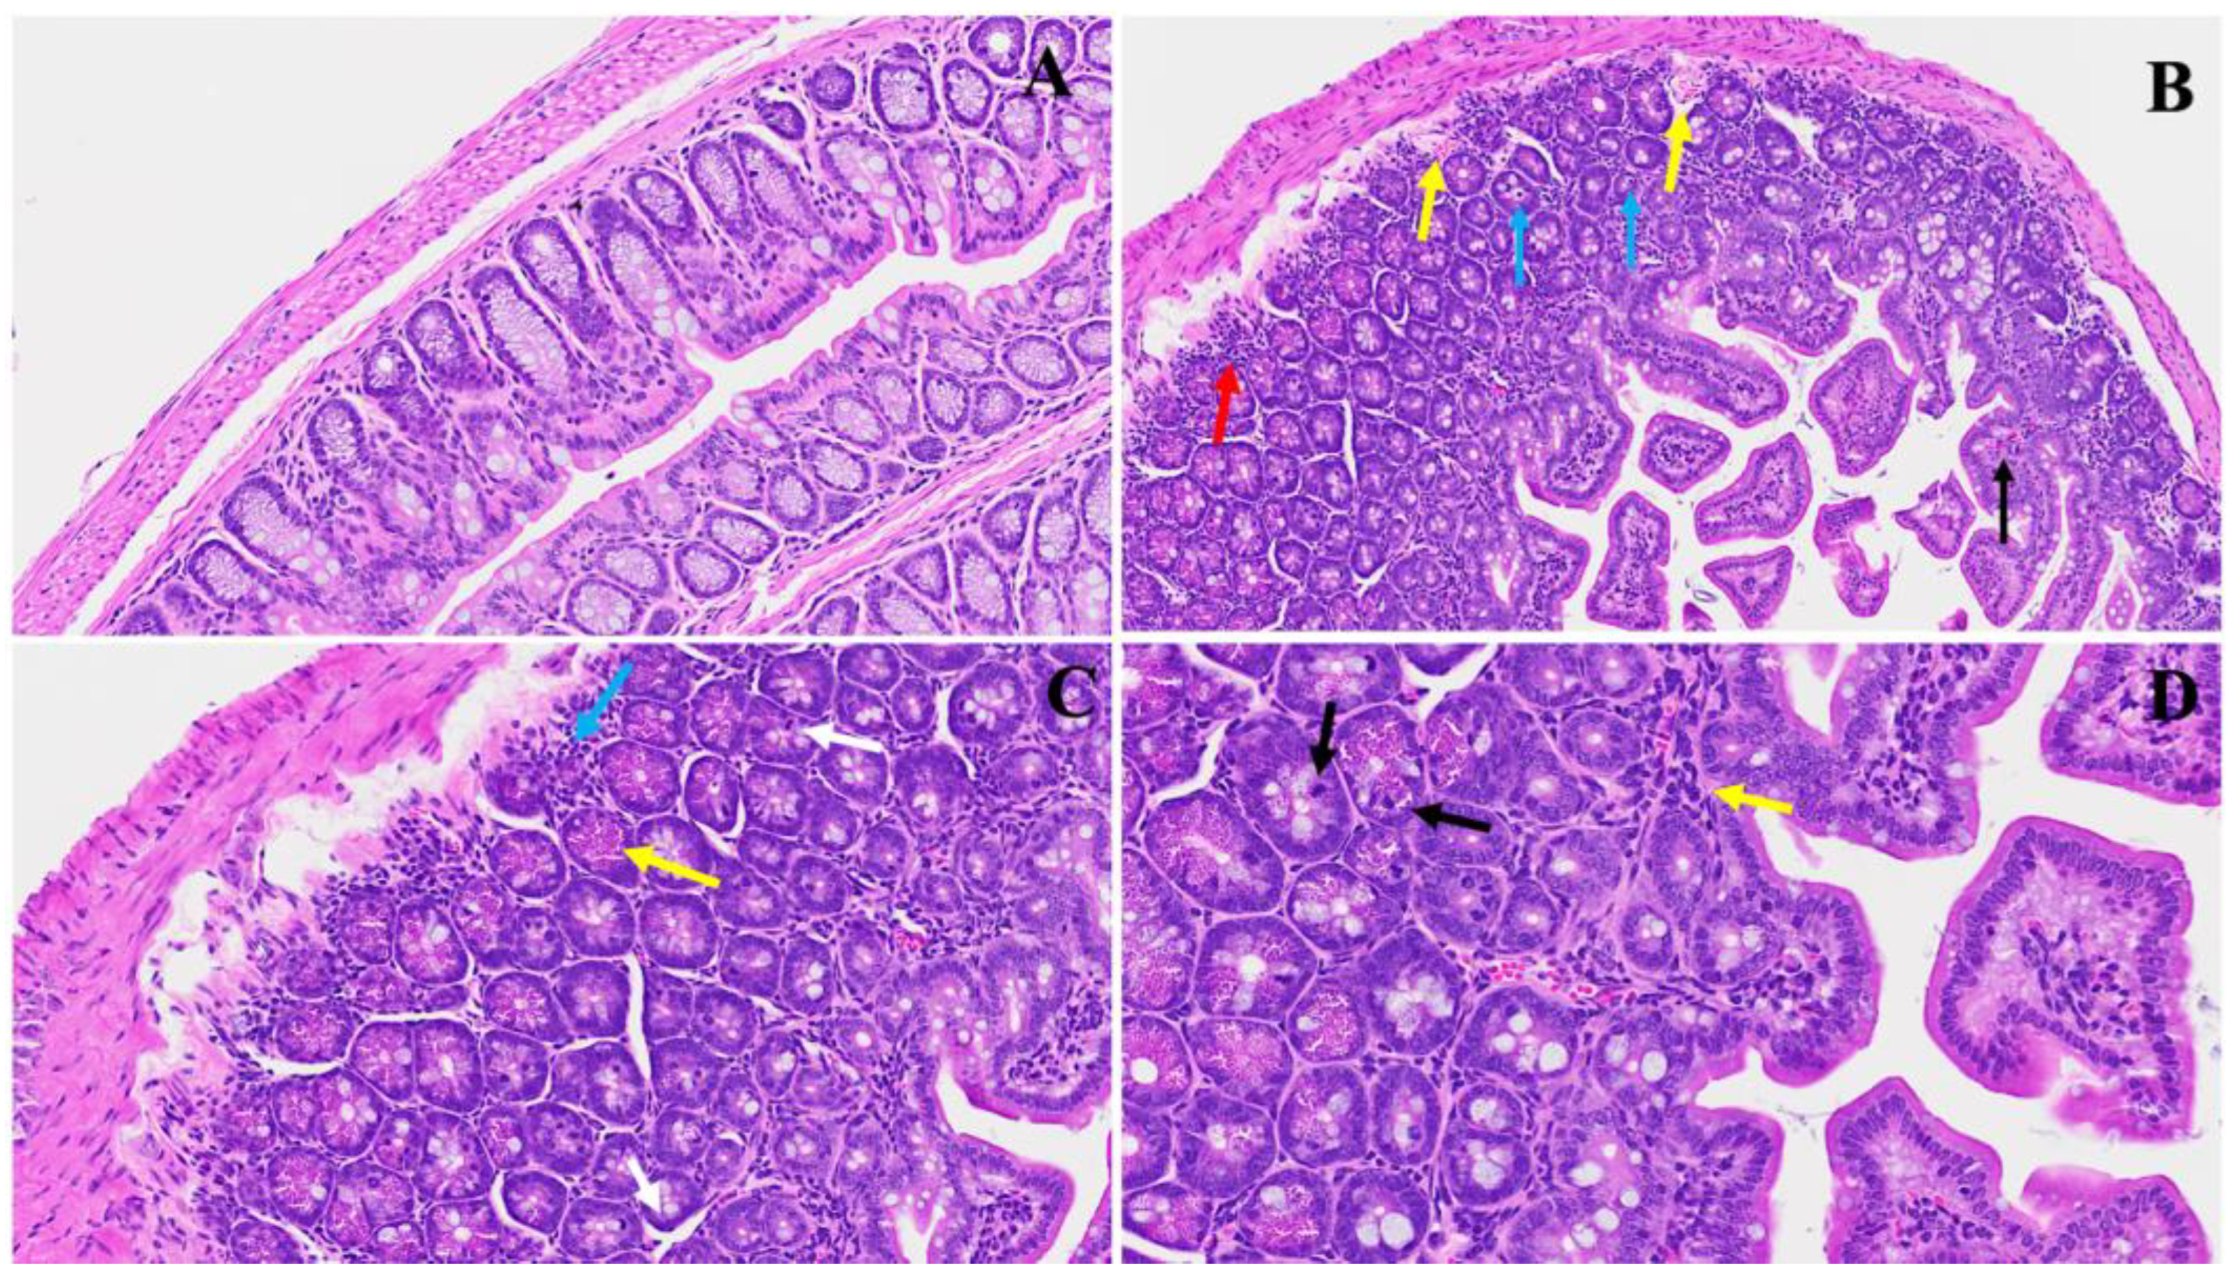

3. Results